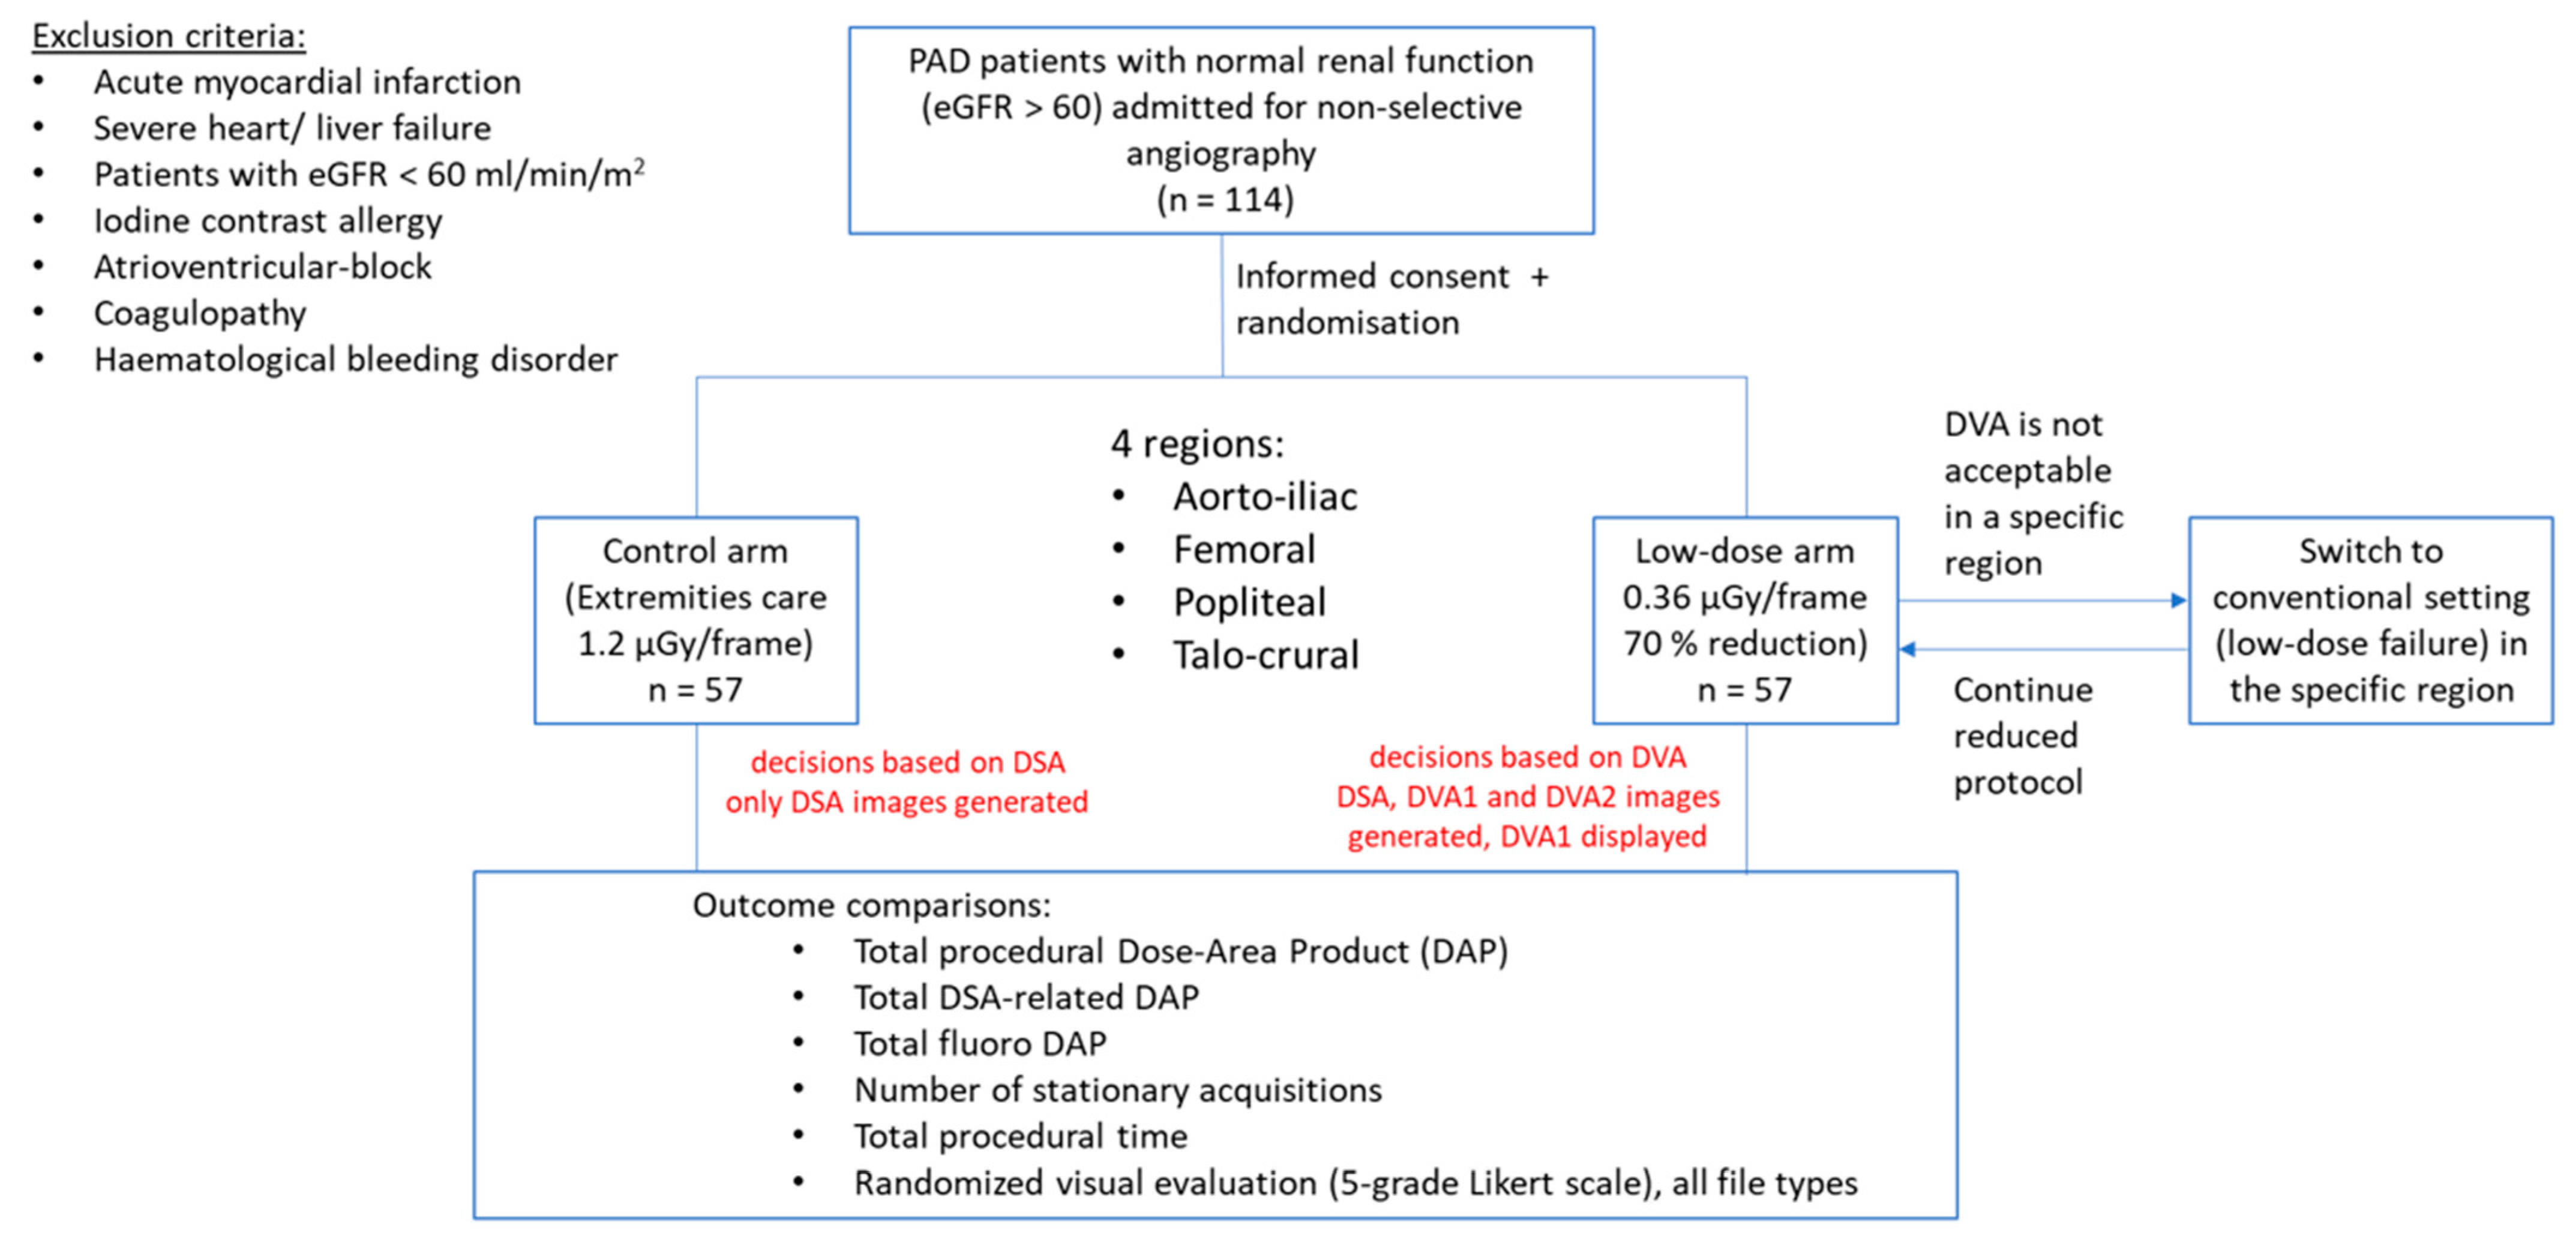

2. Materials and Methods

2.1. Patient Selection

2.2. Study Design

2.3. Image Acquisition

2.4. Image Processing

2.5. Visual Evaluation